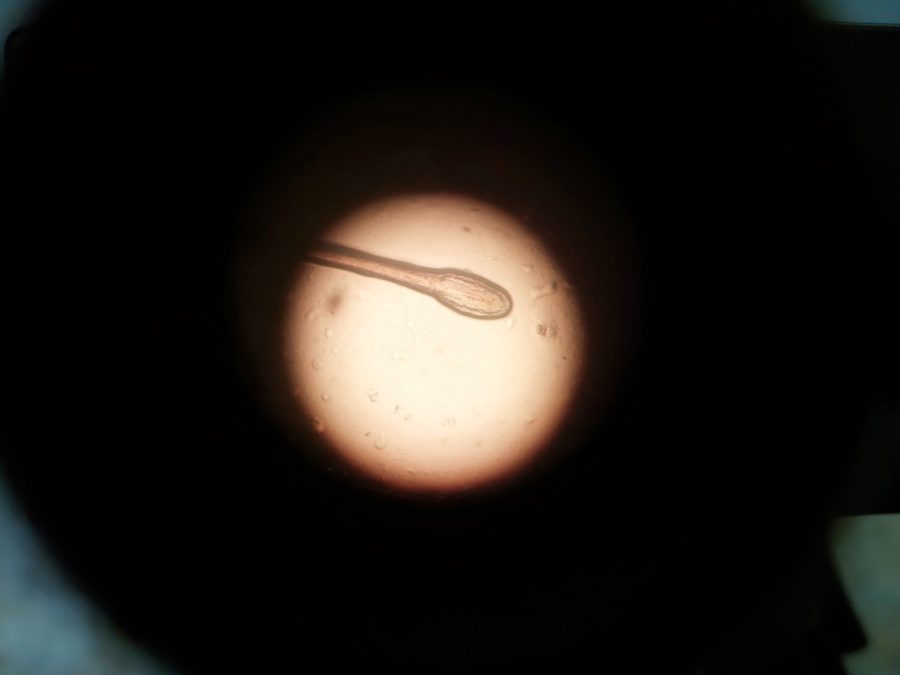

El Mundo Detectan transmisión genética rara por donante de esperma viernes 20, marzo 2026 - 8:12 a. m.